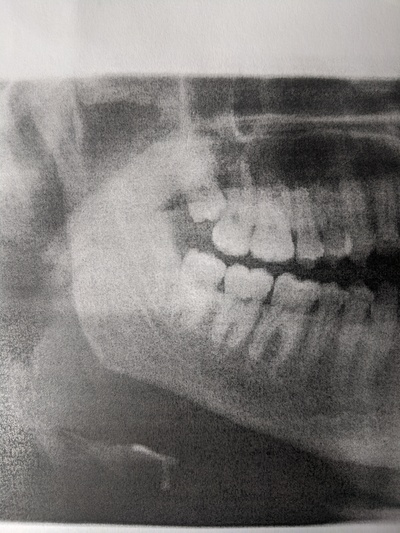

Исполнилось мне 23 годика и вот, в мою ротовую полость постучались они - зубы мудрости. Один из них вёл себя особенно отвратительно, как сосед алкоголик в коммуналке. Рос в щеку, царапал язык, двигал соседей и постоянно болел. После посещения стоматолога было принято решение - выселять его к черту. Я собрала волю в кулак и записалась к лучшему в городе хирургу. Отзывы о нём были неоднозначные: как спец - он просто высший класс, но вот в общении и подходе к клиентам - крайне специфичен. Ну да, не детей с ним крестить, и я выбрала именно его, исходя из профессиональных качеств.

- Ну заходи, раз пришла! - доносится бас из-за двери. И я вхожу. Сажусь и продолжаю дрожать, понимая что всё... Отдаю направления, снимки, а в голове только мысль: "Пропала я!"